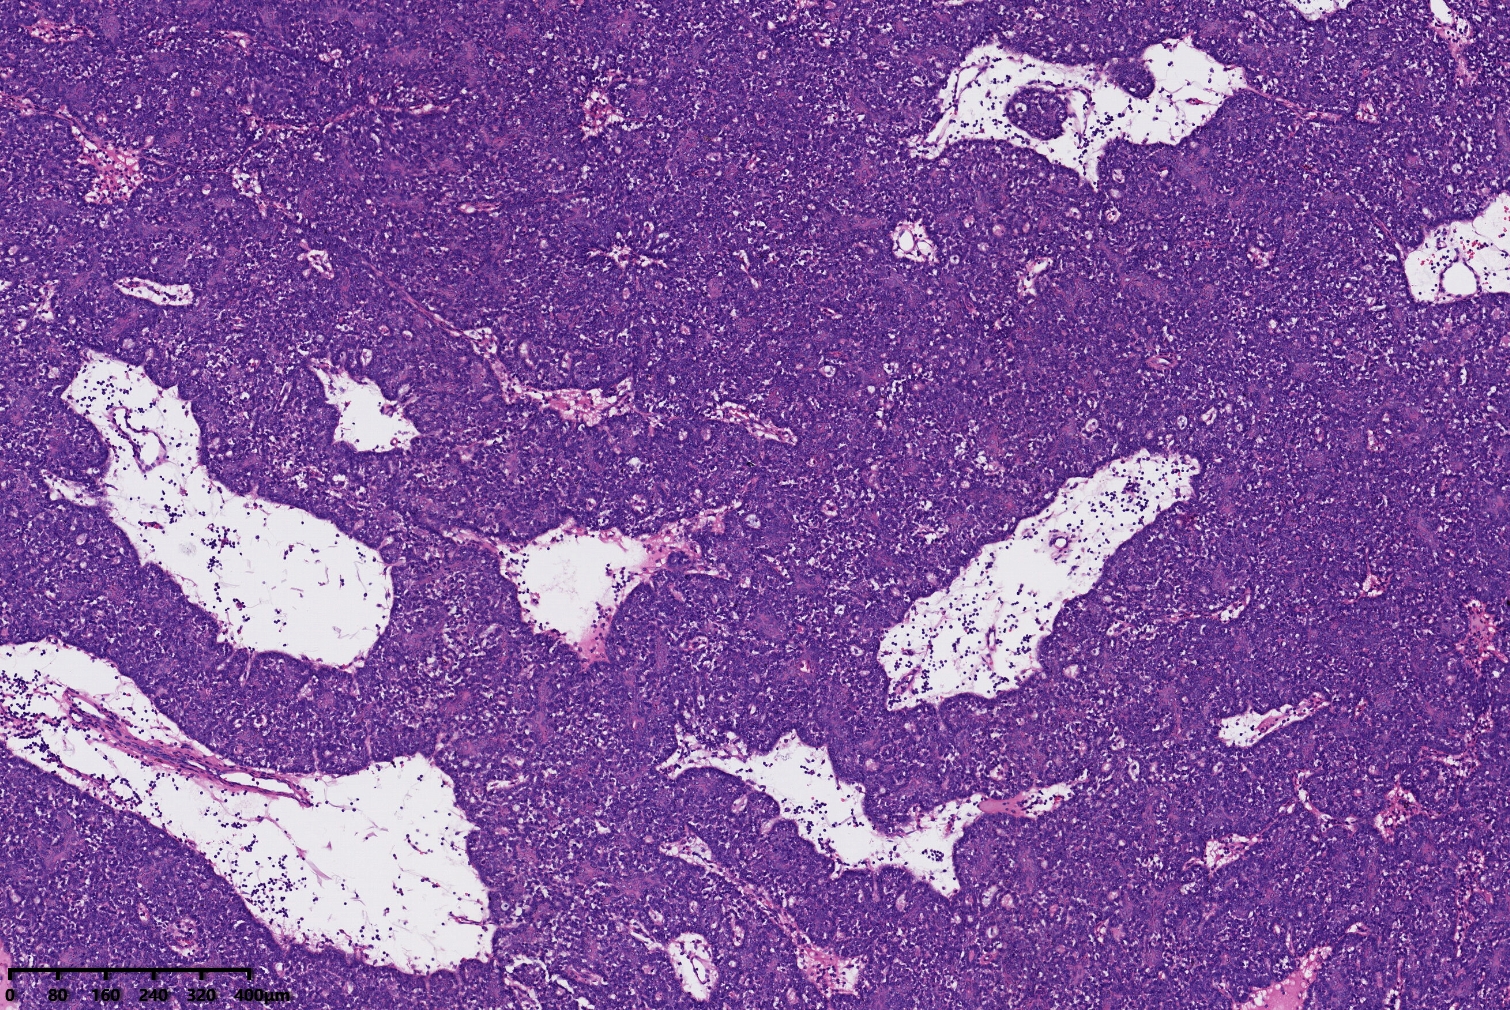

汗腺腺瘤?

背部包块

同意,有的区域像透明细胞汗腺瘤

小汗腺螺旋腺瘤